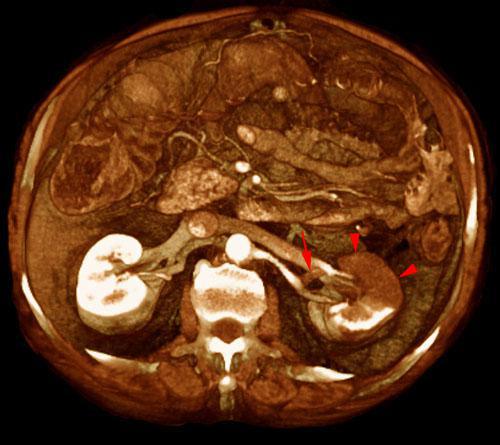

Infarto renal segmentario